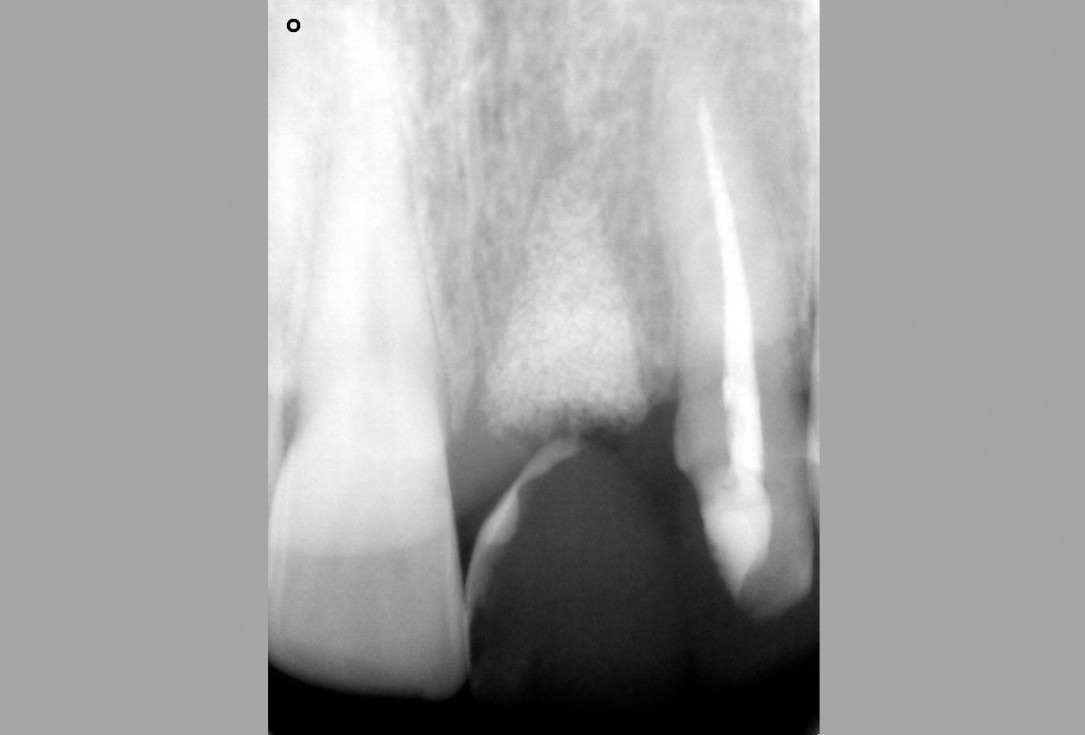

03/16 - Radiograph befor extraction of 21